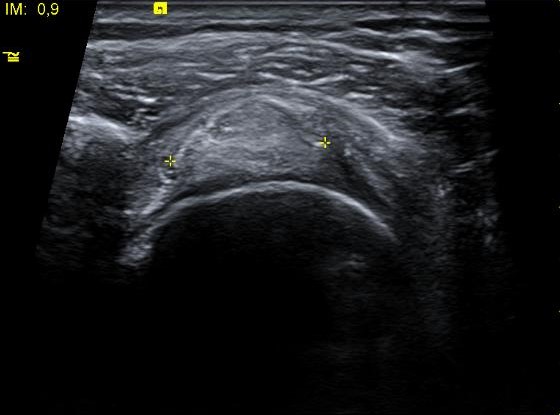

Se visualiza una imagen hiperecoica SIN sombra acústica en el espesor del tendón supraespinoso, lo que orienta hacia calcificación blanda (si fuera dura tendría sombra acústica posterior).